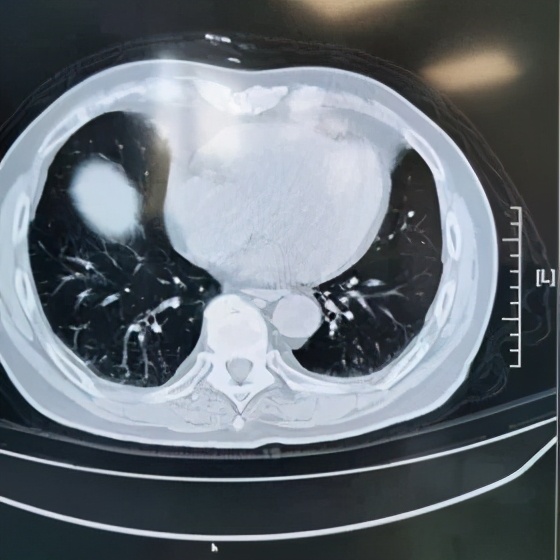

本院胸部CT(2019-08-30)示: 双肺弥漫性间质性改变,有网格状改变、毛玻璃影、局部有支气管牵拉形成支气管扩张的表现。

动脉血气(09-02):PaO2:68mmHg,PaCO2:35mmHg。动脉血气(09-11):PaO2:65mmHg,PaCO2:37mmHg。胸CT和肺功能都指向肺弥漫性间质性病变。

追溯患者2018年体检胸部CT(2018-1-22) :两肺下叶轻度间质增生,无显著双肺弥漫性间质改变。而且近一个月出现气促症状、低氧血症,说明间质性病变有活动性。